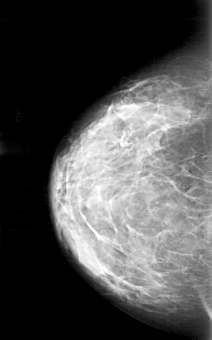

D_4171_1.LEFT_MLO

LEFT_MLO LINES 5161 PIXELS_PER_LINE 3526 BITS_PER_PIXEL 12 RESOLUTION 43.5 OVERLAY

FILE: D_4171_1.LEFT_MLO.OVERLAY

TOTAL_ABNORMALITIES 1

ABNORMALITY 1

LESION_TYPE CALCIFICATION TYPE ROUND_AND_REGULAR-PLEOMORPHIC DISTRIBUTION CLUSTERED

ASSESSMENT 0

SUBTLETY 3

PATHOLOGY BENIGN

TOTAL_OUTLINES 1